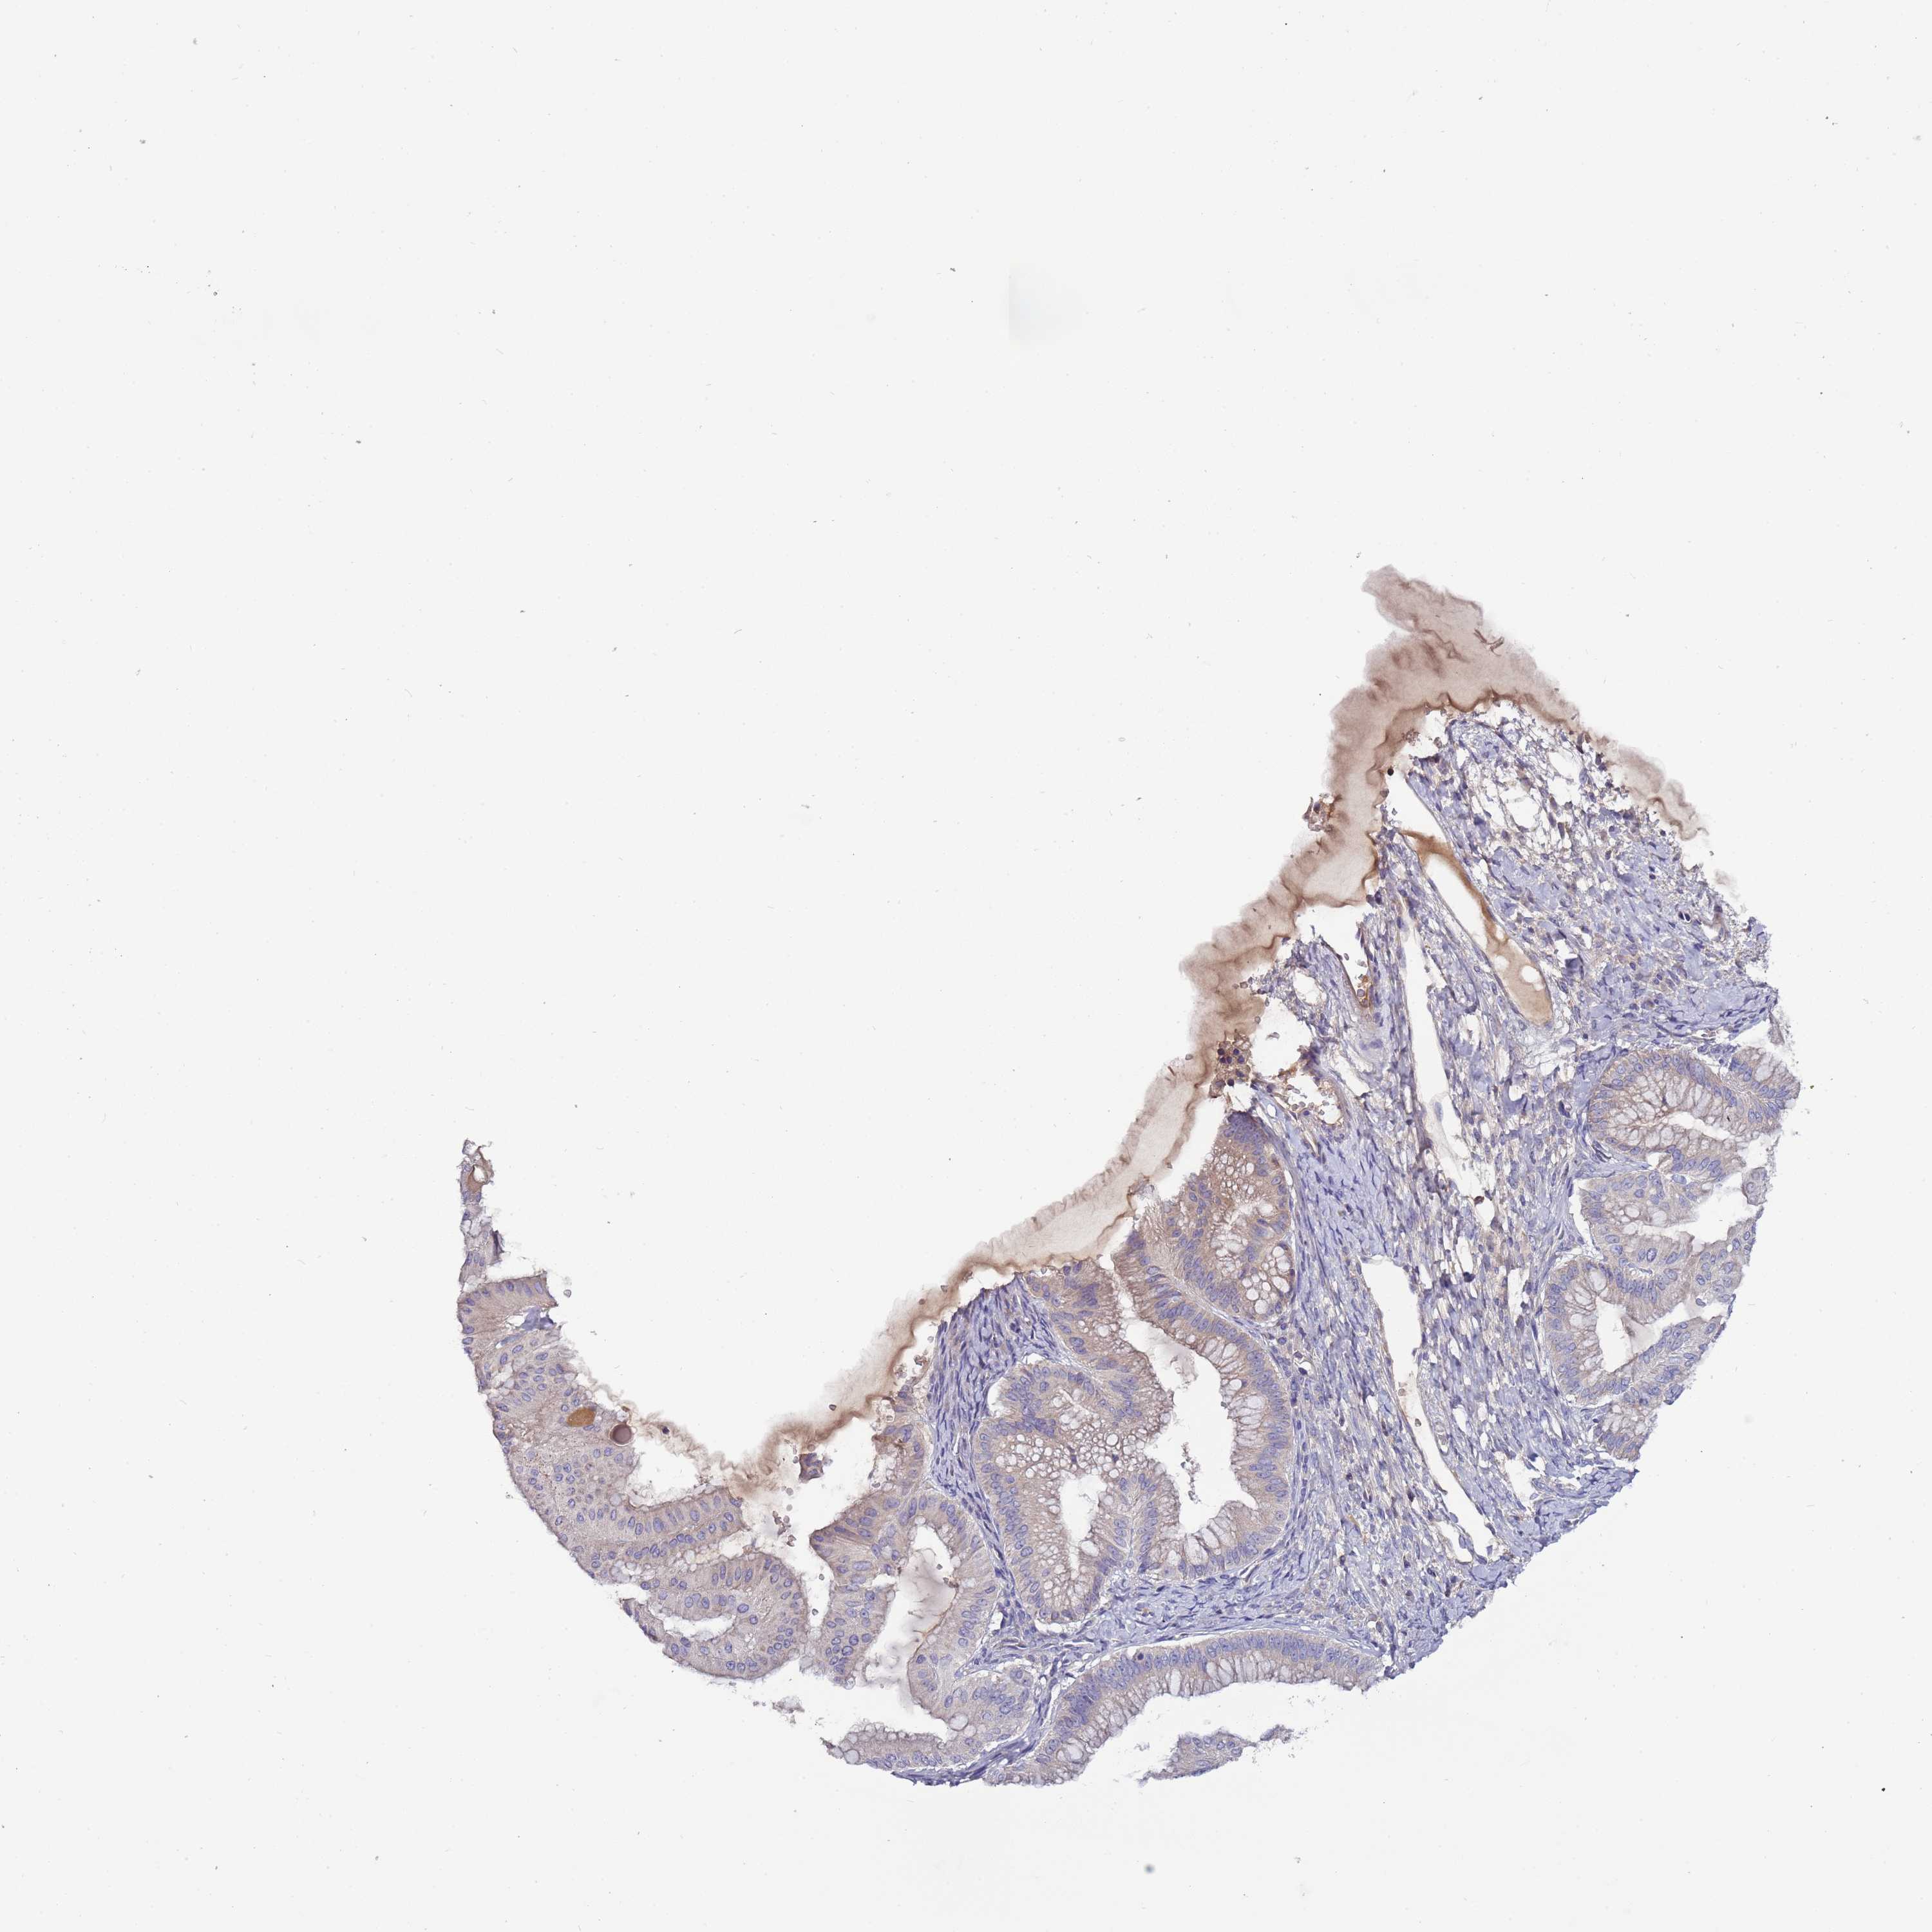

OVARIAN CANCER - Protein expressioni

A mouse-over function shows sample information and annotation data. Click on an image to view it in a full screen mode. Samples can be filtered based on level of antibody staining by selecting one or several of the following categories: high, medium, low and not detected. The assay and annotation is described here.

Note that samples used for immunohistochemistry by the Human Protein Atlas do not correspond to samples in the TCGA dataset.

Antibody stainingi

Antibody staining in the annotated cell types in the current human tissue is reported as not detected, low, medium, or high, based on conventional immunohistochemistry profiling in selected tissues. This score is based on the combination of the staining intensity and fraction of stained cells.

Each image is clickable and will lead to virtual microscopy that enables deeper exploration of all samples and also displays staining intensity scores, fraction scores and subcellular localization as well as patient and tissue information for each sample.

Antibody HPA048615

Staining

High

Medium

Low

Not detected

Intensity

Strong

Moderate

Weak

Negative

Quantity

>75%

75%-25%

<25%

None

Location

Nuclear

Cytoplasmic/membranous

Cytoplasmic/membranous,nuclear

Cystadenocarcinoma, serous, NOS

Carcinoma, NOS

Cystadenocarcinoma, mucinous, NOS

Carcinoma, endometroid